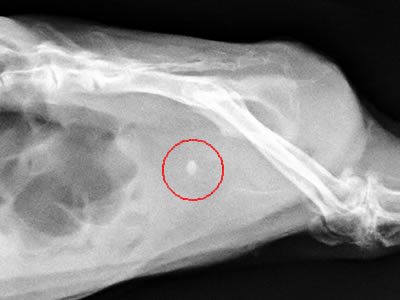

- Röntgenbild eines Meerschweinchens mit einem Blasenstein (im roten Kreis zu sehen)